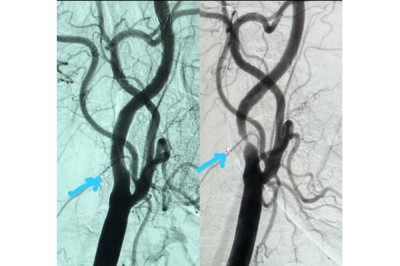

Interventional Cardiologist successfully performs a rare Carotid Stent